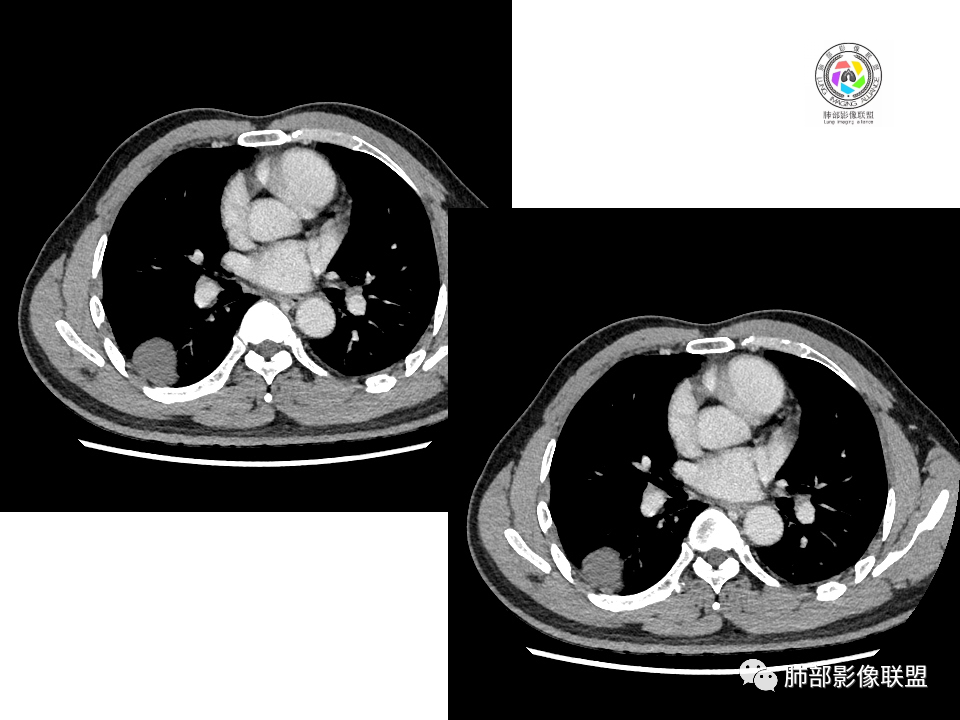

血管也是稍推移,在边缘,病灶密度均匀,边缘稍收缩;均匀强化;

这两个病灶的密度、强化、形态、边缘、与血管的关系类似;还是一元论吧。

2.右肺下叶背段胸膜下块影,边界清楚光整,上下极见磨玻璃晕,未见明显分叶毛刺和棘状突起,未见胸膜凹陷或胸壁侵入。密度均匀,轻度不均匀强化。未见支气管进入。

4.右肺下叶基底段支气管血管束旁小结节影,边界清楚,强化不明显。注意,这结节在“遥远的”基底段。

1.边缘光整干净,大病灶缺乏坏死等,不符合鳞癌影像学特征。尽管有吸烟史,还是偏年轻。

2.边缘光整,会是小细胞癌或是大细胞癌吗?小细胞癌的肺门纵隔淋巴结增大往往十分夸张,该患者不符合。

注意,基底段支气管血管束旁的小结节影,即便是淋巴结,也与背段病灶引流途径不符。

3.会是转移瘤吗?如前所述,患者偏年轻,缺乏相关原发肿瘤病史,强化程度不高,似乎也缺乏支持点。

4.良性占位绕不过去,如发生于该部位的孤立性纤维瘤等……

5.慢性感染灶。缺乏临床表现,强化不显著会想到继发性肺结核,背段病灶过于光整均匀,周边过于干净使人狐疑,且“成掎角之势”的中叶病灶结核灶特点也着实不多。

有老师分析,多发病灶有磨玻璃晕,可以符合隐球菌感染,确实如此。但背段边缘如此锐利的块影还是更容易让人联想到新生物。

1、普通人隐球菌感染的时相:初期的隐球菌感染周围有晕,晕从多变少,或包裹,或吸收,结节实性区可迅速变大。后期(慢性期)的隐球菌周围无明显晕征,边界较清楚。

3、卫星灶与“蘑菇兄弟”:诊断隐球菌时,建议找卫星灶,卫星灶可以在遥远的地方。可以是遥远地方的微小结节——“小蘑菇兄弟”。有些远处的卫星灶,通常是不规则饱满实性的,晕征不明显。隐球菌的卫星灶非常“隐”,但发现率高达60%多,诊断价值高。

5、周围毛刺纤维、边缘形态等:坏死包裹会使得结节变圆;结节多缺乏明显的分叶征,缺乏局部突出生长能力;如果出现分叶,是由多处肉芽肿中心形成。没有坏死的局限化,结节只是凑合在一起,常呈方形征;毛刺进入晕区(概念源自南边老师),毛刺较短、较软;周围的晕吸收后,会留下不规则边,外面常残留丝状条索;收缩力较弱,临近胸膜对胸膜牵拉不明显。